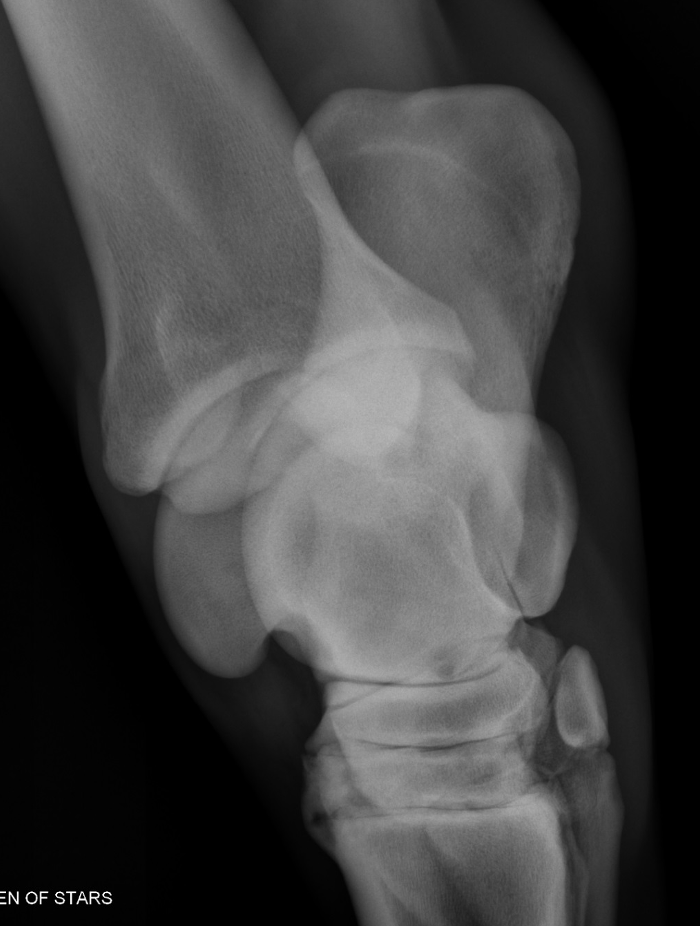

What is shown in these images?

epiphyseal septic arthritis and osteomyelitis -lots of swelling -destruction of joint space -lots of fragmentation -gas pockets